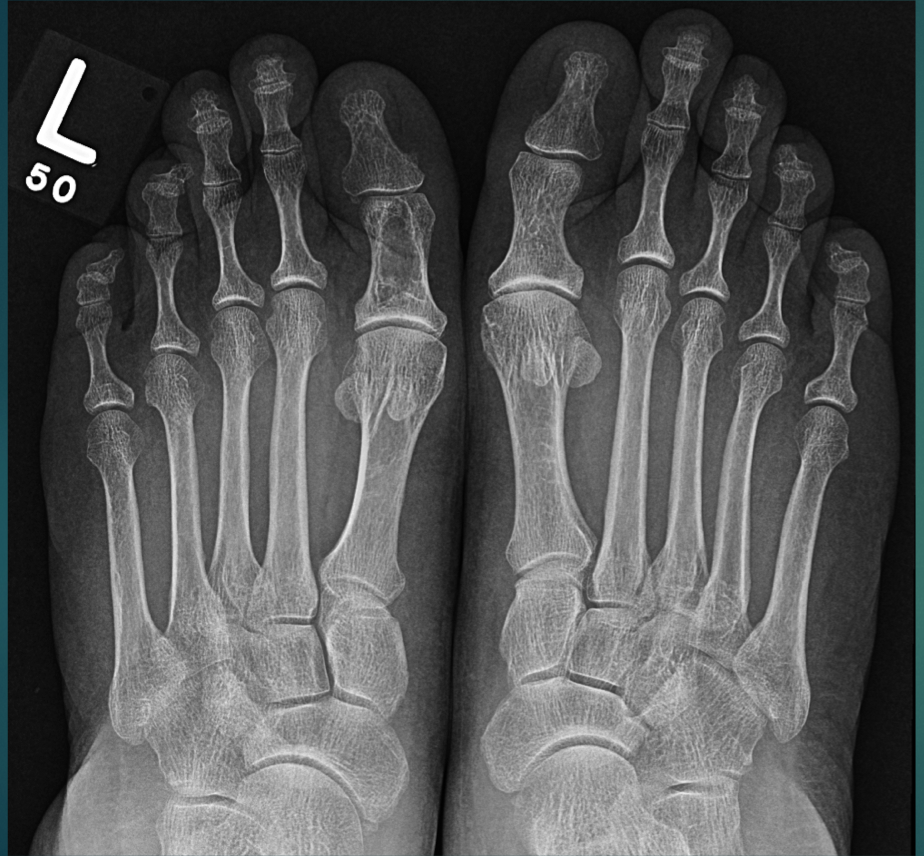

50 YO M. Weakness, fatigue, back pain.

Multiple, punched out, osteolytic lesions

think: MM or mets